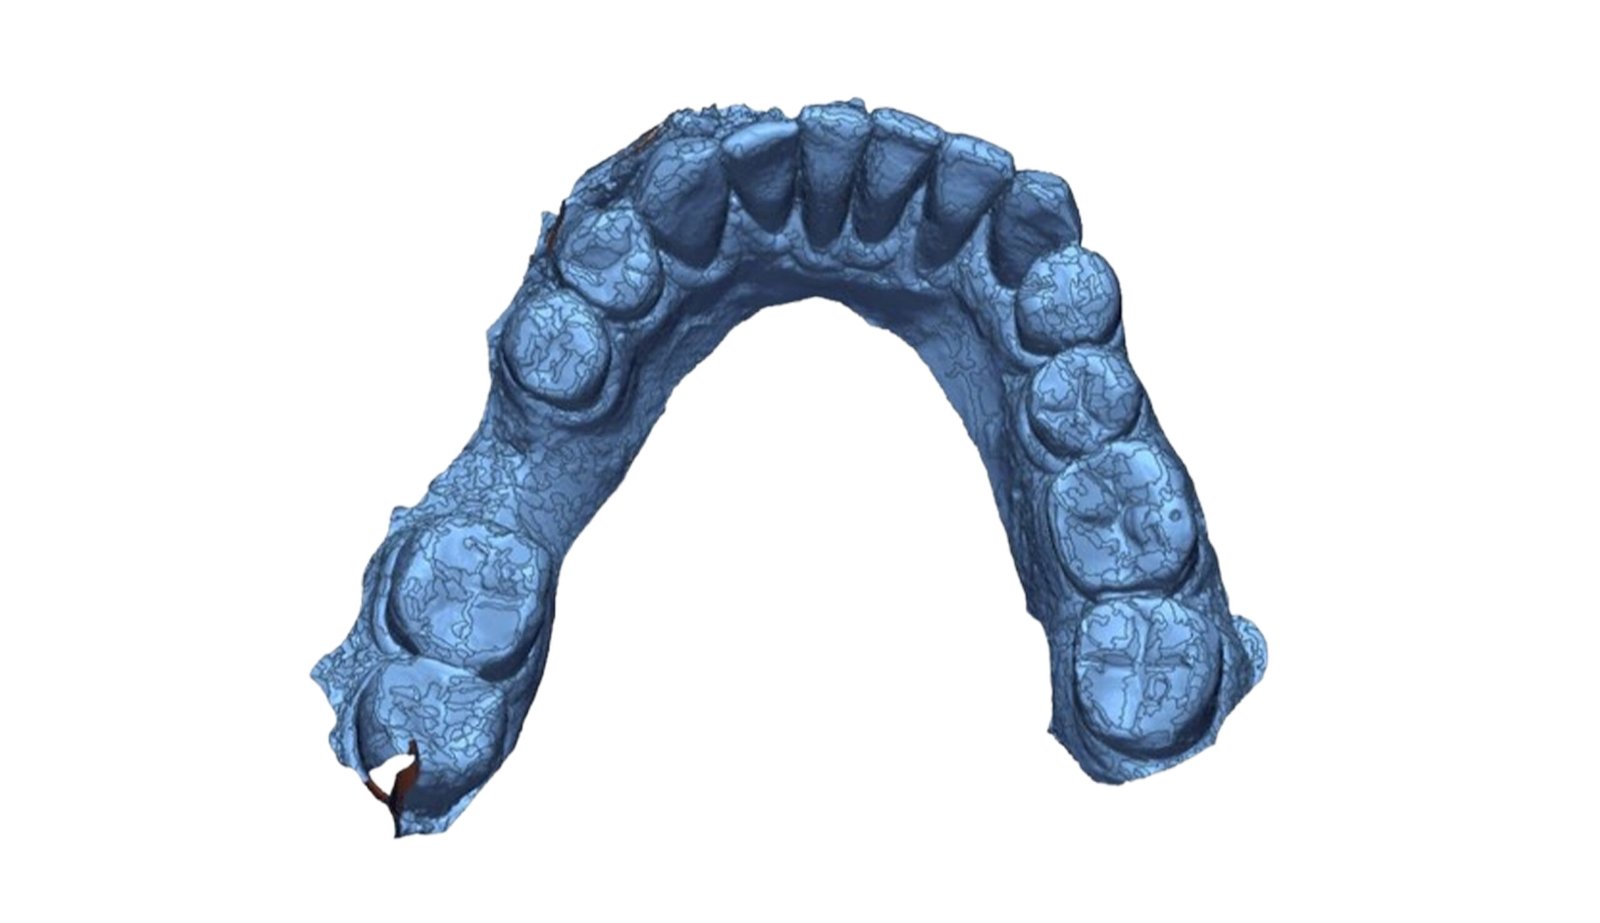

This section specializes in high-precision 3D deviation mapping to compare pre- and post-treatment anatomical or implant-related geometries. Using advanced superimposition and deviation algorithms, we quantify micro-level shifts, deformation zones, and structural discrepancies with sub-millimeter accuracy. These analyses support quality control, surgical verification, and design validation. The resulting deviation heat-maps provide clear, data-driven insights that enhance clinical decision-making and device optimization.